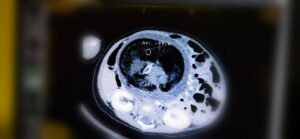

عملية جراحية نادرة في المستشفى السلطاني لاستئصال جنين من داخل جنين

أجرى قسم جراحة الأطفال بالمستشفى السلطاني عملية جراحية نادرة تتمثل في استئصال جنين من داخل جنين، وهي حالة تعد نادرة الحدوث عالميًا؛ لكونها تتم في ظروف استثنائية. .

يُذكر أن هذه الظاهرة الطبية تُعرف بـ

” Fetus in feto “

وتحدث بنسبة 1 من كل 500 ألف حالة ولادة حية على مستوى العالم.